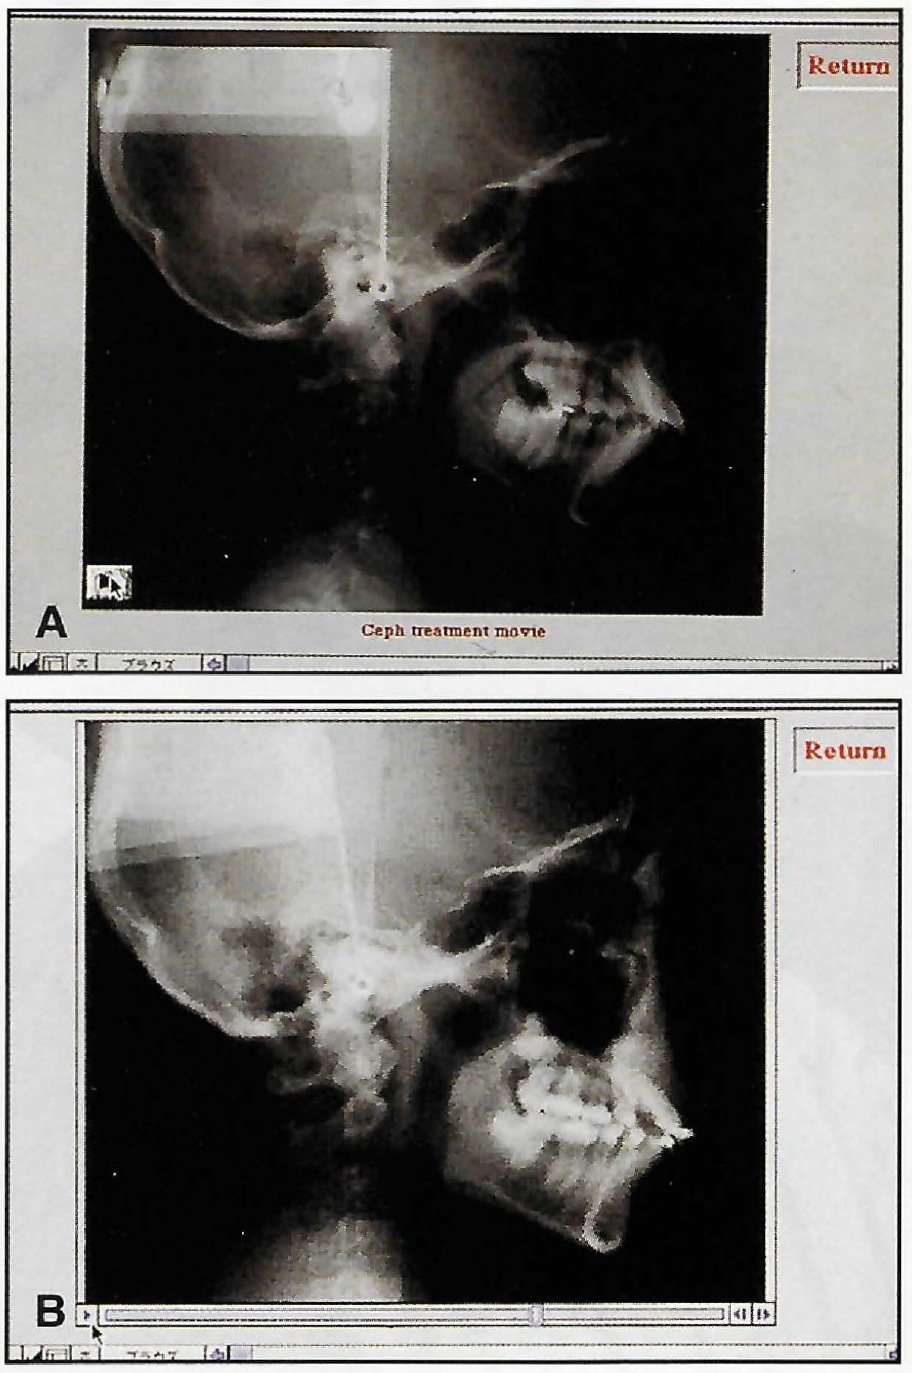

Treatment was completed in 11 months, using 111 sets of aligners ([img=6A]Fig. 6A, B[/img) and C.

Fig. 6 A. Patient after 11 months of treatment. B. Superimposition of pre- and post-treatment cephalometric tracings (continued in next image).

Fig. 6 (cont.) C. Post-treatment ClinCheck records.